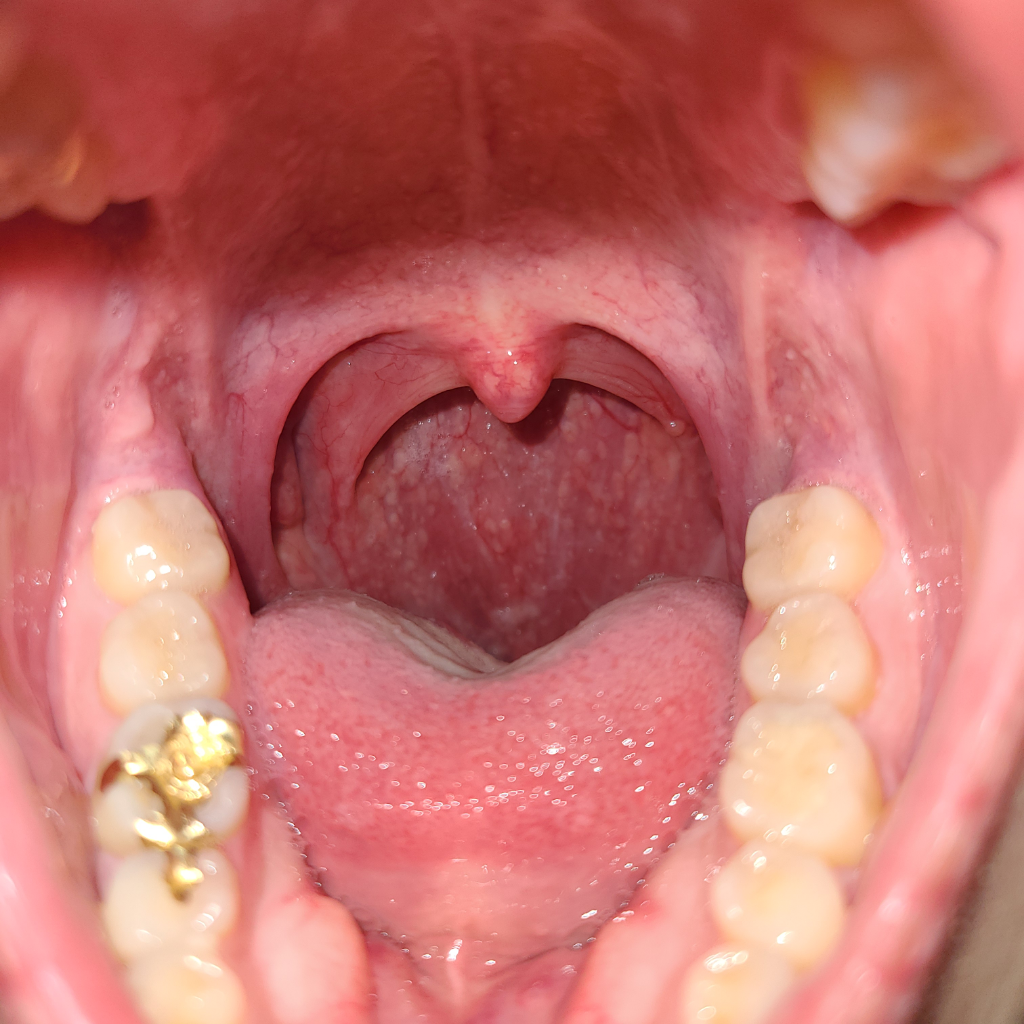

안녕하세요. 강성주 의사입니다.

명확한 부종은 관찰되지 않습니다.

일부 불편감이 있으실 경우는 역류성 식도염 및 후두염 등에 대한 진단을 위해 가까운 내과 및 이비인후과에 내원해 보시는 것을 추천드립니다.

감사합니다.